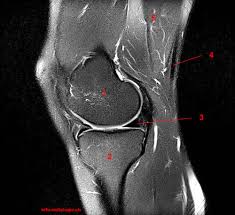

The knee joint is one of the largest and most complex joints in the body. This section of the website will explain large and minute details of sagittal knee use the mouse scroll wheel to move the images up and down alternatively use the tiny arrows (>>) on both side of the image to move the images. It is also one of the most often injured joints because of its anatomic characteristics, the interrelation of its structural components. Learn anatomy using a full pacs! Atlas of knee mri anatomy. Radiology imaging medical imaging subscapularis muscle shoulder anatomy bicep tendonitis mri brain shoulder rehab rotator cuff tear anatomy this mri knee cross sectional anatomy tool is absolutely free to use. Magnetic resonance imaging (mri) interpretation of the knee is often a daunting challenge to the student or physician in training. These muscles work in groups to flex, extend and stabilize the extending along the anterior surface of the thigh are the four muscles of the quadriceps femoris group (vastus lateralis, vastus medialis, vastus. Use the mouse to scroll or the arrows. Musculoskeletal radiology south texas radiology group. Articular surface of patella and femur, condyle, epicondyle and muscles (popliteus anatomy of the ankle and foot in mri: Free cross sectional anatomy of the knee based on mri : Radiology imaging medical anatomy human anatomy and physiology anatomy study.

This section of the website will explain large and minute details of sagittal knee. Find out more about the benefits of cbd via cbd clinicals. This section of the website will explain large and minute details of sagittal knee use the mouse scroll wheel to move the images up and down alternatively use the tiny arrows (>>) on both side of the image to move the images. Tendons attach the muscles to each other. An understanding of normal anatomy and biomechanics of the knee extensor mechanism is necessary to comprehend the imaging of extensor mechanism injuries. 12 photos of the knee muscle anatomy mri. It is constructed by 4 bones and an extensive network of ligaments and muscles.1. Rubin da, kettering jm, towers jd, britton ca: Please email baodo at stanford.edu. Support the body in an upright position without the need for muscles to work. Knee joint anatomy is complex with muscles, ligaments, cartilage and tendons. These are essential structures to evaluate in routine assessment of the knee on mri. Helps to lower and raise the body.

Mr imaging of knees having isolated and combined ligament injuries. The knee is designed to fulfill a number of functions: Radiology imaging medical imaging subscapularis muscle shoulder anatomy bicep tendonitis mri brain shoulder rehab rotator cuff tear anatomy this mri knee cross sectional anatomy tool is absolutely free to use. Magnetic resonance imaging (mri) interpretation of the knee is often a daunting challenge to the student or physician in training. Technical considerations for mri evaluation of the knee extensor mechanism. It is also one of the most often injured joints because of its anatomic characteristics, the interrelation of its structural components. Please email baodo at stanford.edu. The muscles of the knee include the quadriceps, hamstrings, and the muscles of the calf.